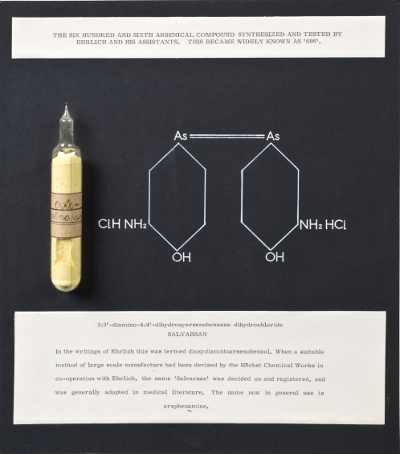

1911年

一篇论文描述用salvarsan(胂凡钠明)治疗"慢性天胞疮",salvarsan是第一个抗微生物药物。用药两天之后,疾病消失了。不久,Paul Ehrlich同样使用这个"神奇的子弹"(magic bullet)治疗了一名患梅毒的士兵。这个药物是Ehrlich尝试过的第606个化合物,所以又名"606"。因为副作用巨大,606很快被青霉素淘汰,但依然是重大的科学突破。